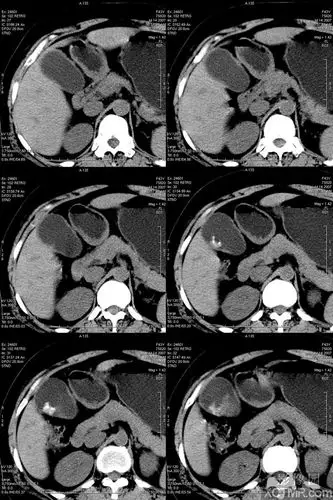

慢性胆囊炎并胆囊结石ct病例图片影像诊断分析